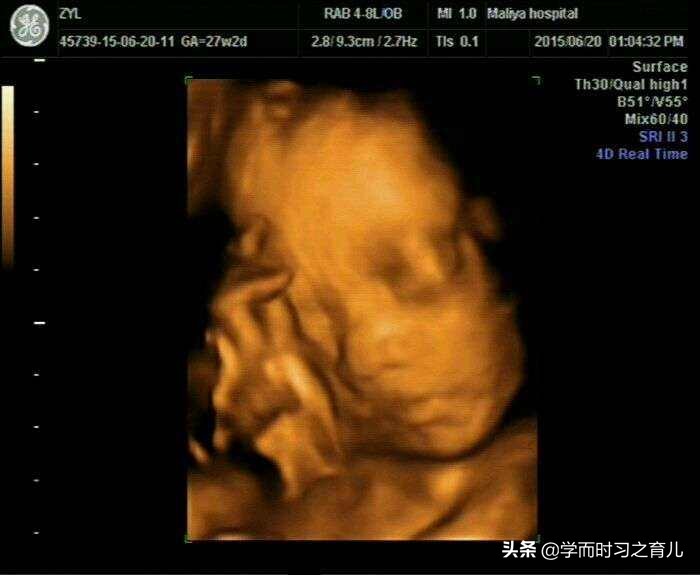

2、胎儿总是挡住脸

其实四维彩超对胎儿面部的检查内容还是比较多的,比如嘴巴、鼻子等等,但如果胎儿总是用手挡住脸,那医生就无法看清其局部发育情况,从而导致产检不顺利。

此外,针对这种现象,准妈妈是最无奈的,因为宝宝挡住脸,不像宝宝动得厉害,准妈妈还可以调整一下,一般宝宝挡住脸,孕妈咪不管做什么,宝宝都不会那么挺好的配合,当然了,有些宝宝比较听话,妈妈一说,宝宝就放下手了。